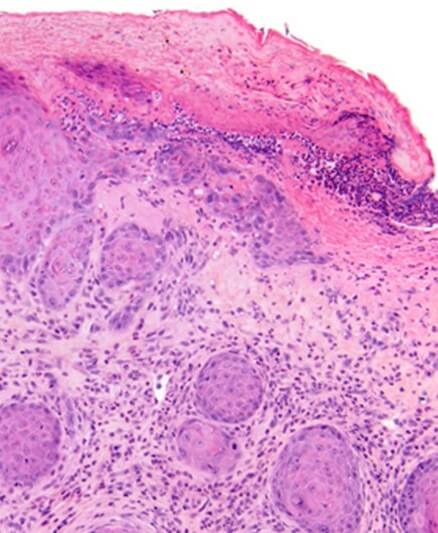

Another issue that occurs quite commonly is clinicians sending biopsies of ulcerated skin to evaluate for suspected inflammatory or neoplastic skin lesions. Ulceration can pose difficulties in evaluating for both types of lesions. Sending a small/partial biopsy of ulcerated skin can cause diagnostic difficulties in squamoproliferative lesions. For example, if the clinical impression is squamous cell carcinoma in situ (Bowen’s Disease) then sending a biopsy of wholly ulcerated skin is not going to provide any useful diagnostic information. Ulceration can also pose diagnostic challenges in deeper lesions. This is because reactive atypia and epidermal hyperplasia can occur in the setting of ulceration, see Figures 2 & 3, and differentiating this from a well differentiated squamous cell carcinoma in a small/partial biopsy may be very difficult.

![This image depicts is this lesion benign (reactive squamous hyperplasia) or it it a well differentiated squamous cell carcinoma?. Professional medical imaging for clinical reference and educational purposes. [umbracoNodeId=18662]](/assets/image/jpeg/is-this-lesion-benign-reactive-squamous-hyperplasia-or-it-it-a-well-differentiated-squamous-cell-carcinoma-1iccv1vinei1kbtgnccqzx.jpg)

Figure 2. Is this lesion benign (reactive squamous hyperplasia) or it it a well differentiated squamous cell carcinoma?